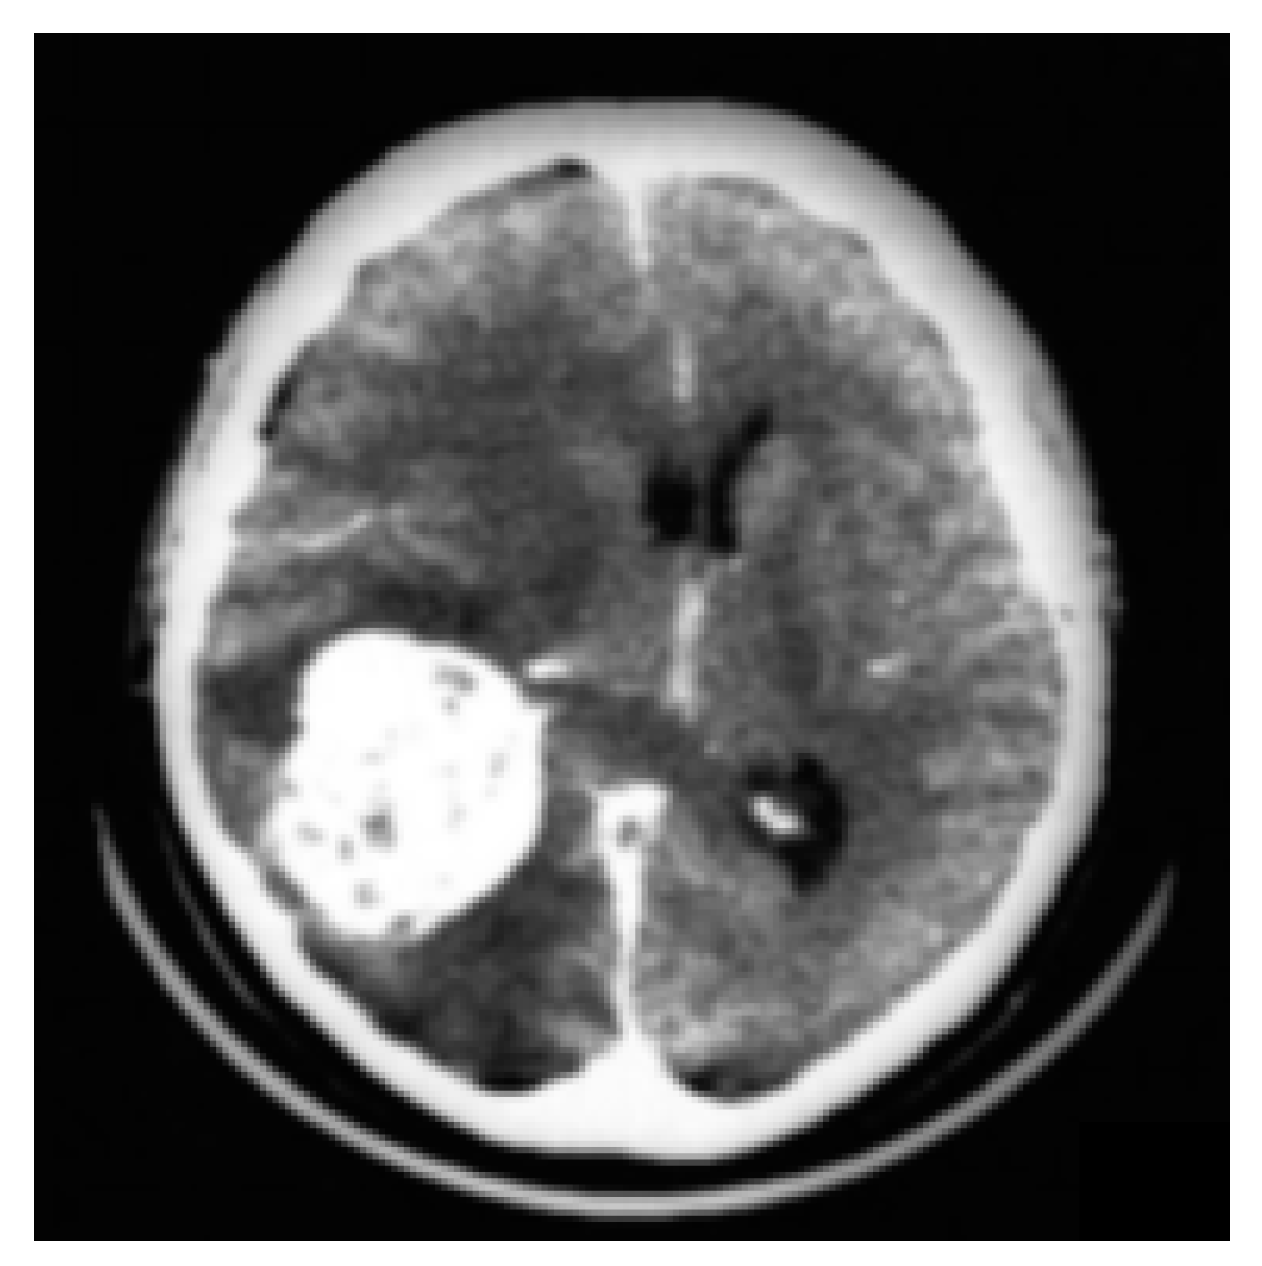

3.2. CT